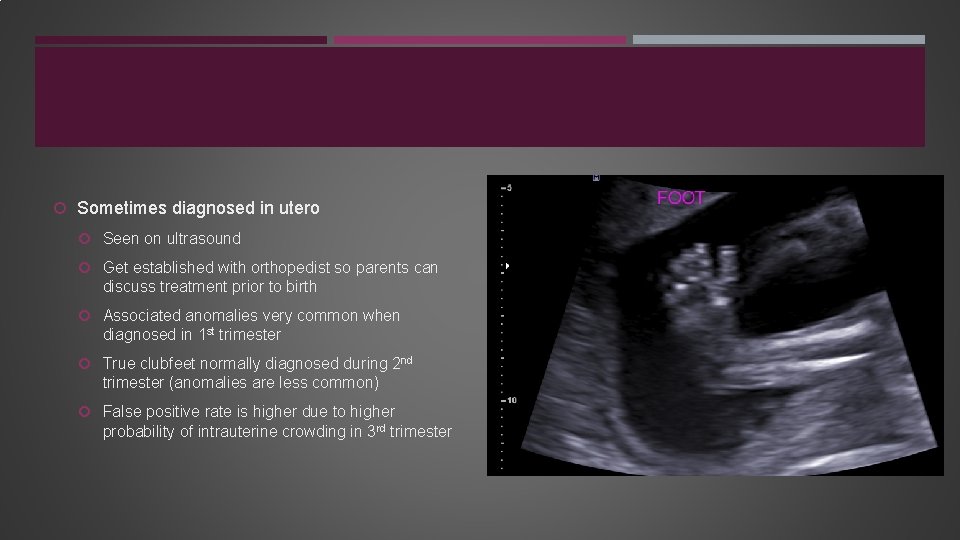

Sometimes diagnosed in utero Seen on ultrasound Get established with orthopedist so parents can discuss treatment prior to birth Associated anomalies very common when diagnosed in 1 st trimester True clubfeet normally diagnosed during 2 nd trimester (anomalies are less common) False positive rate is higher due to higher probability of intrauterine crowding in 3 rd trimester